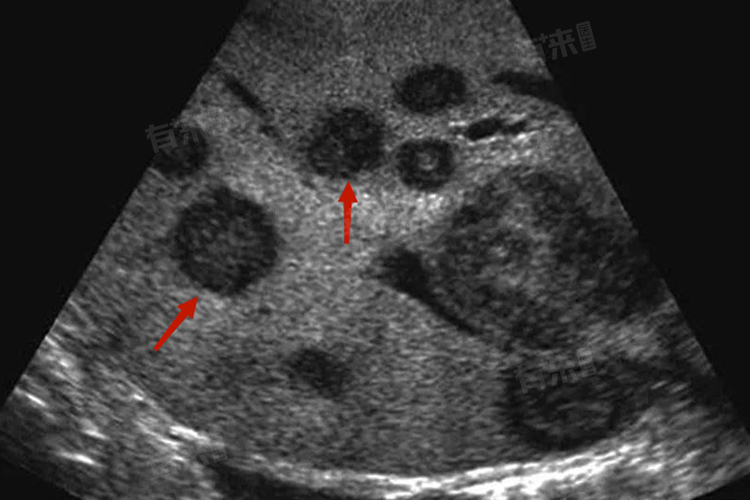

- 多样性:转移瘤可以发生在身体的任何部位,常见的转移部位包括肺、肝、骨、脑等。